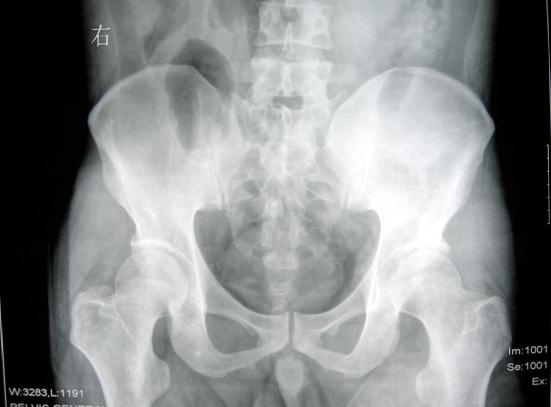

株洲男子被钢板砸到右下肢连同右侧半骨盆完全离断……现实版死神来了